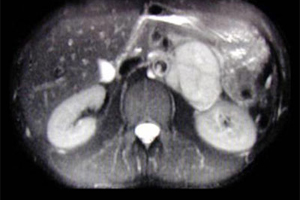

نخستین بار عمل جراحی لاپاراسکوپی فئوکروموسیتوما (غدد فوق کلیه) در کاشان انجام شد.

به گزارش خبرگزاری صدا و سیما،سرپرست مجتمع بیمارستانی شهید بهشتی شهرستان کاشان گفت: دکتر مسعود بنایی فلوشیپ لاپاراسکوپی خانم 52 ساله که تشخیص فئوکروموسیتومای آدرنال چپ با توده ی حدود 4-5 سانتی متر بر روی غده فوق کلیه چپ داده آن شده بود ،با روش لاپاراسکوپی تحت جراحی برداشتن آدرنال چپ قرار داد .

مهران شریفی افزود : این تومور ترشح کننده ترکیبات کاته - کولامینی (افزایش دهنده فشار خون) با علائم افزایش فشارخون، تپش قلب، سردرد و تعریق است که در 90 درصد موارد از غده آدرنال (فوق کلیوی) منشا می گیرد.

وی با بیان این که بهترین روش درمان این بیماران، روش لاپاراسکوپیک است، گفت :در این شیوه نیاز به باز کردن شکم نیست و با عوارض و درد کمتری، زمان بستری بیمار را کاهش می یابد .